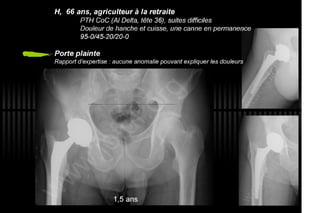

2013 032. Douleur sur PTH céramique-céramique

032. Douleur sur PTH céramique-céramique - Painfull THA with Alumine-Alumine bearing